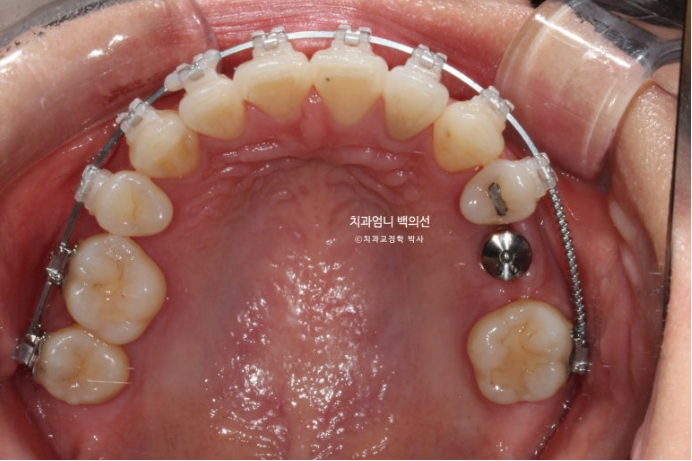

치료 시작 1년 3개월차 결손된 큰어금니 공간이 충분히 확보가 되어 드디어 임플란트를 식립했습니다.

24.11